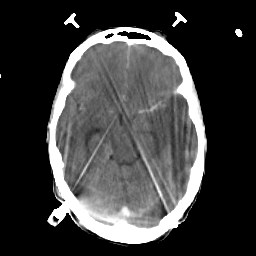

Metastatic bronchogenic carcinoma: Roentgen-ray CT -- Slice #8

[Home][Help][Clinical] Slice 8